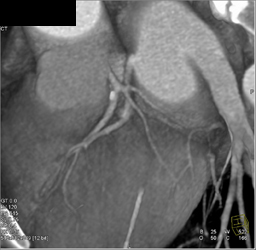

Dilated Left Ventricle